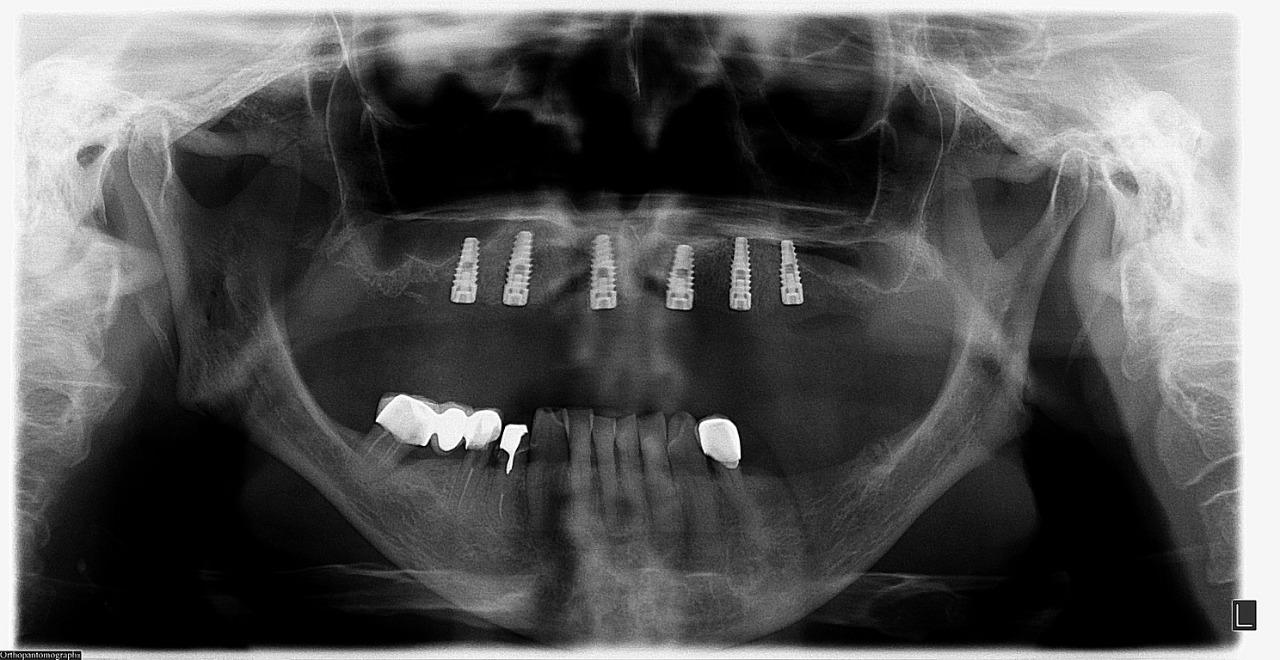

Prótesis híbrida

Son prótesis sin paladar que va fija a unos implantes, por lo tanto no es removible. Es el tratamiento perfecto para pacientes que están cansados de tener prótesis totales, donde no pueden tener buena masticación y degustación de los alimentos.